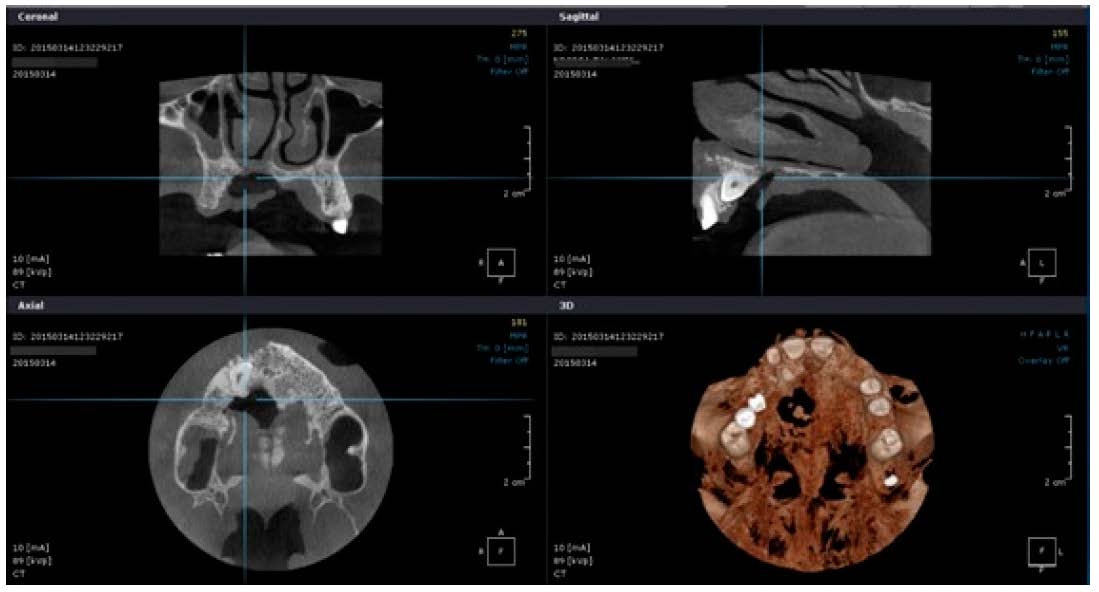

The first therapeutic step was the cleaning of the wound with antiseptic solutions—Povidone-Iodine 10% and Chlorhexidine Digluconate 0.2%, followed by suture removal and curettage of the necrotic tissues. The palatal bone could be identified without periosteum. In depth, the nasal cavity was exposed, and nasal secretions were leaking to the oral cavity. For the certain diagnostic to be confirmed, a full maxillary Cone Beam Computer Tomography (CBCT) exploration was performed (Figure 3 and Figure 4).

Figure 3.

Oronasal communication: Cone Beam Computer Tomography (CBCT) aspect.

Figure 4.

Oronasal communication: CBCT virtual 3D reconstruction.